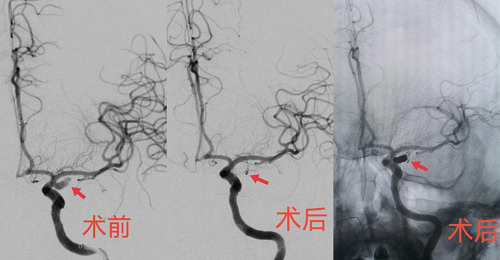

术中三维造影显示左侧不规则后交通动脉瘤,顶端可见子瘤,约3.3*8mm,手术难度及风险相当大。脑血管病介入团队采取了双微导管交替栓塞技术,经过2个小时的手术,患者这颗颅内“不定时炸弹”被成功拆除。过程顺利,动脉瘤达到致密栓塞,载瘤动脉及后交通动脉通畅。术后患者转入ICU接受术后治疗。

▲术后即刻造影,动脉瘤致密栓塞,载瘤动脉通畅